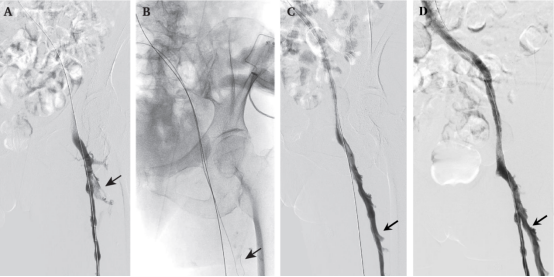

image.png 黑色箭头所指处即为股深静脉,通过介入治疗后血栓彻底清除

在既往下肢深静脉血栓的介入治疗中,只针对顺行静脉造影可见的腘静脉、股浅静脉、股总静脉和髂静脉进行治疗,对顺行造影无法显影的股深静脉,其血栓常被忽视。

仁济医院血管外科张岚团队在原有介入治疗基础上,创新性通过逆向方式寻找到股深静脉,对股深静脉血栓进行彻底清除,使血栓的远期并发症率从28%下降至10%,大幅提高了介入治疗的长期疗效。